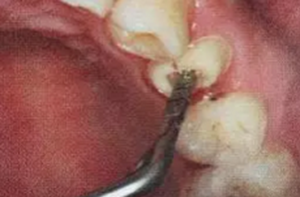

纖維樁修復(fù)之精細(xì)操作

(根管內(nèi)殘留物)

個(gè)人見解:必要的情況下先開闊根管口建立一定的視角后,慢速手機(jī)上G鉆為引導(dǎo)鉆,由號(hào)遞增引導(dǎo)開闊通路;P鉆預(yù)備樁道,同樣需要由小向大號(hào)遞增,直到選擇好適合的號(hào)預(yù)備到規(guī)定測(cè)量的深度即可,再配合纖維樁系統(tǒng)中各型號(hào)纖維樁所匹配的樁道鉆,預(yù)備、修整成與纖維樁相適應(yīng)的樁道。

預(yù)備后根管壁上會(huì)不同程度的牙膠和封閉劑等殘留物,所以樁道預(yù)備前后建議X線片輔助檢查預(yù)備深度等情況,而殘留物也會(huì)很清晰地顯現(xiàn)。